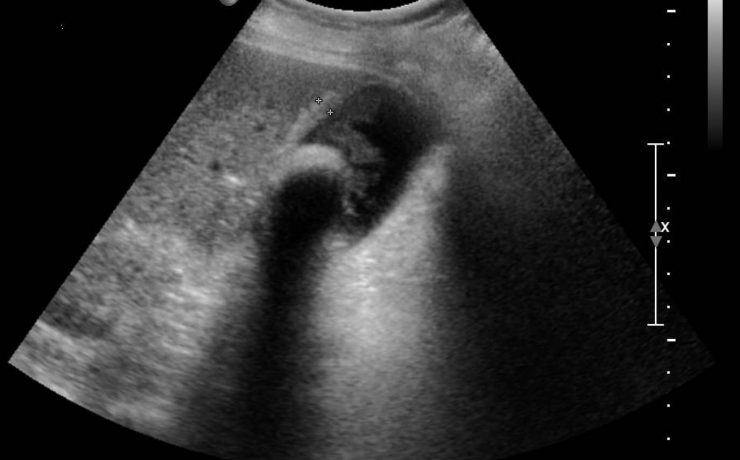

Hiperplasia prostática benigna

La hiperplasia prostática benigna (HPB) es muy prevalente en atención primaria; es el principal motivo de consulta por problemas urológicos en el hombre y es el primer diagnóstico que debemos pensar ante un paciente mayor de 50 años que consulta por síntomas obstructivos y/o irritativos. El diagnóstico de HPB es